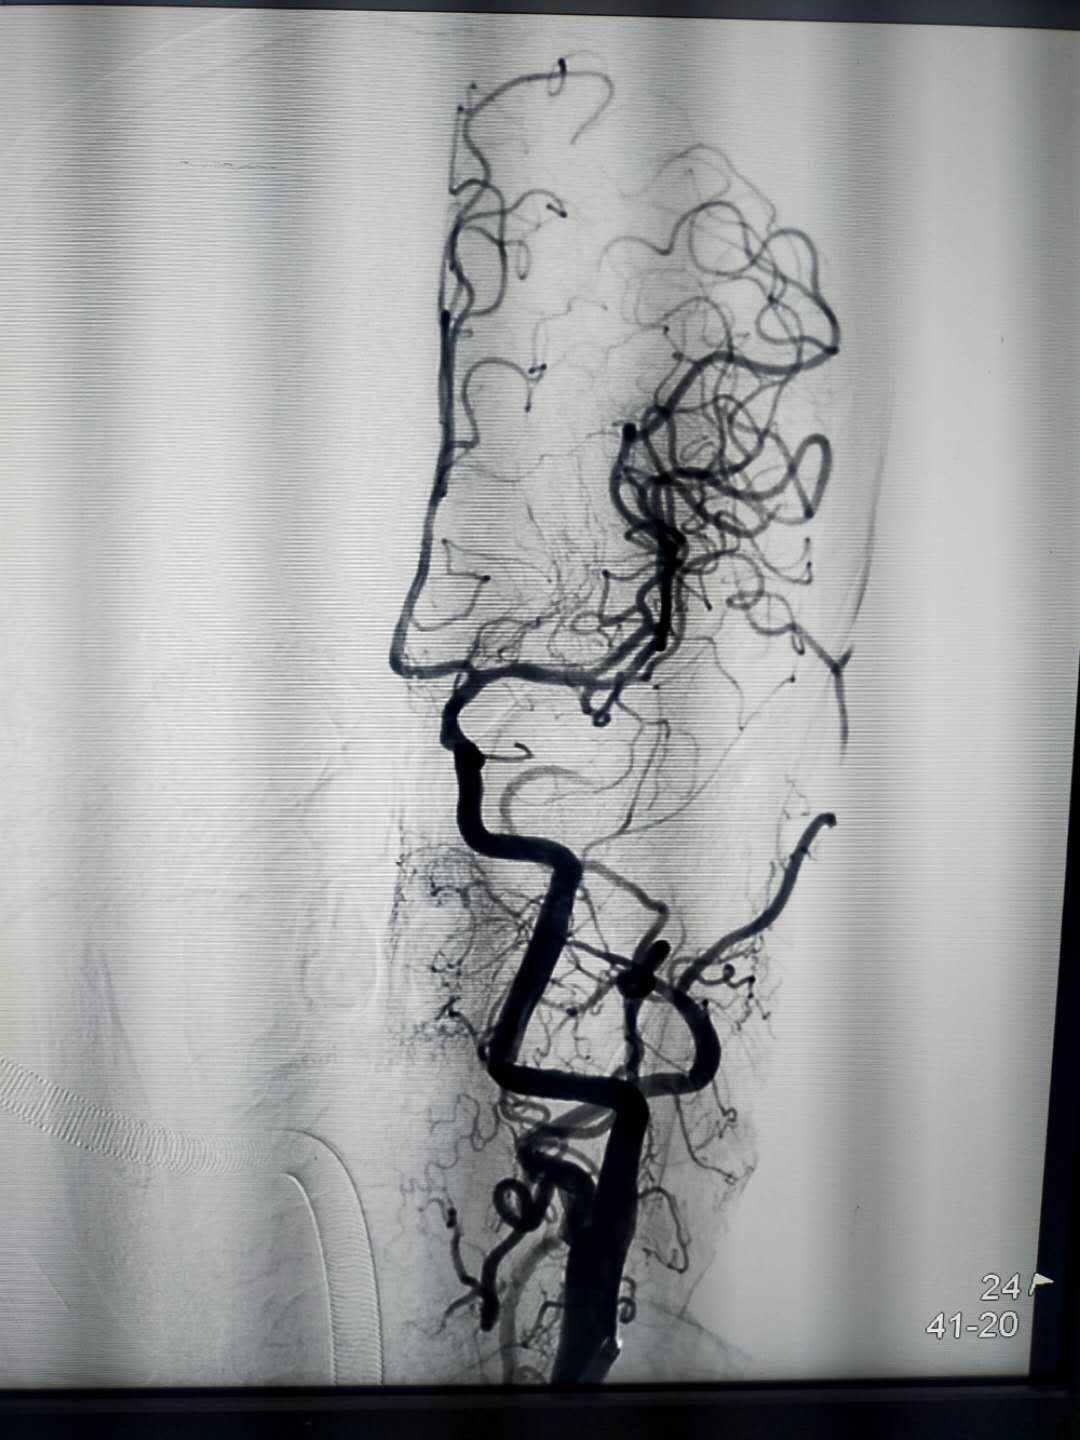

经检查,王大爷被诊断为:右颈总动脉—大脑中动脉M2血管闭塞。

(抽吸前)

造影提示右侧颈总动脉起始部约3cm以上闭塞,立即送入椎动脉导管,插入闭塞血管近段抽吸血栓。

抽吸过程中,面临血管负荷大、血管迂回、抽吸困难、再次血栓形成等困难。定信心,绷紧弦、加把劲,面对难度系数100%的手术,王敏波团队坚定“咬定青山不放松、不破楼兰终不还”的信念,想尽一切办法抽吸血栓。

心往一处想,劲往一处使。在王敏波团队的努力下,历经2小时5分钟的奋战,7次抽吸,4次支架,难关终于被攻克。